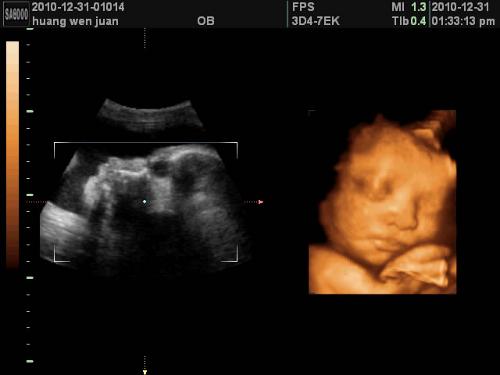

专家表示:医生通过超声波判断胎盘成熟度,主要依据胎盘上的钙化点来判断胎盘成熟度,钙化点散在就诊断为2级,钙化点连成片就断为3级,这多少会受医生主观因素影响,也许有的医生看是3级,在有的医生那儿就只能达到2级。